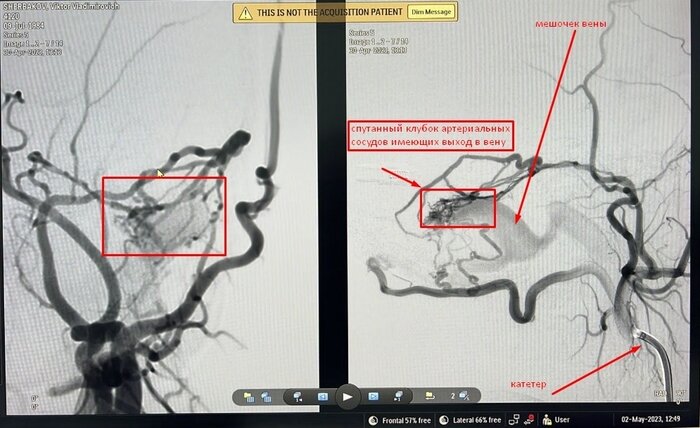

Примерно год назад, утром, лежа в постели я услышал прерывистый звук в левой части головы, совпадающий с ритмом моего сердца- ззык- ззык (тиннитус). Изменив положение головы он исчез. Постепенно, в течение 6 месяцев ситуация пришла к тому, что звук стал громче, и смена положения в лежачем состоянии перестала отключать звук. Звук уже присутствовал и вертикальном положении, но был тише и менее заметен, иногда он мог исчезнуть на несколько дней и появиться вновь, звук был разный, завывающий, прерывистый, пульсирующий, шипящий, свистящий и т.д. Привыкнуть к нему было не возможно. Я пошел по врачам, делал МРТ, и КТ проходил разные процедуры- массаж, капельницы, бросил пить, бросил курить, знаялся спортом. Но ничего не помогало.Никто не мог сказать точную причину и диагноз. В итоге я попал на прием к отоневрлогу, который проверил мой слух и заключил что причина в сосудах, и нужна консультация сосудистого хирурга. К тому времени я уже плохо спал из-за громкого звука, и мне назанчили миртел, с ним я спал более менее. Сосудистый хирург (Коспанов Нурсултан Айдарханович- спасибо вам огромное) предложил сделать церебральную ангиографию- это когда через бедренную артерию вводят катетр, который проходя через большую артерию, заходит в голову, далее через данный катетер вводят контрастное вещество и под рентегном делающим 4 кадра в секунду смотрят картину сосудов. Там то и обнаружилась причина - Дуральная артериовенозная фистула — редкая причина пульсирующего шума в ухе. Если кратко - то это врожденный порок развития сосудов (0, 17 % на 100000 населения), когда артериальные сосуды имеют прямое сообщение с венозными сосудами. Из-за огромной скорости кровотока в артерии, кровь попадая ввену создает эти шумы. Эти звуки были слышны даже моей жене, приложив ухо к моему лбу. Через 2 месяца мне сделали операцию, так же, через бедренную артерию, под общим наркозом ввели длинный катетер, и с помощью него выпустили специальный клей, который заклеил аномальные проходы между сосудами. Операция длилась 40 минут. Всё прошло успешно, теперь я сплю хорошо. Огромное спасибо врачам и нашему казахстанскому хирургу Мынжылкы Бердиходжаеву, который выполнил эту операцию- внутрисосудистая эмболизация путем эндоваскулярной хирургии.